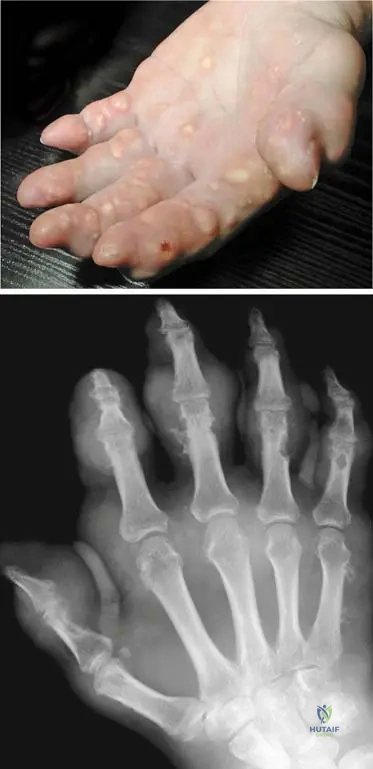

A 75-year-old male with poorly controlled gout for several decades presents with multiple firm, non-tender nodules in his palmar region.

Correct Answer: C

Rationale: The clinical context for Fig. 7.3 a, b explicitly states, "Late stage of gout: numerous subcutaneous tophi are present in the palmar region." Tophi are characteristic subcutaneous deposits of urate crystals in chronic, uncontrolled gout. Heberden's and Bouchard's nodes are associated with osteoarthritis, and rheumatoid nodules with rheumatoid arthritis.

Question 40

A 72-year-old male with a history of chronic gout presents with hand pain. Radiographs reveal soft tissue masses around the small joints of the hand.

View Answer & Explanation

Rationale: The clinical context for Fig. 7.3 b states, "These tophaceus gouty deposits are also visible in the radiograph around the small joints of the hand." Tophi are the hallmark of late-stage chronic gout and can appear as soft tissue masses on radiographs. Chondrocalcinosis is calcification of cartilage, typically associated with pseudogout.